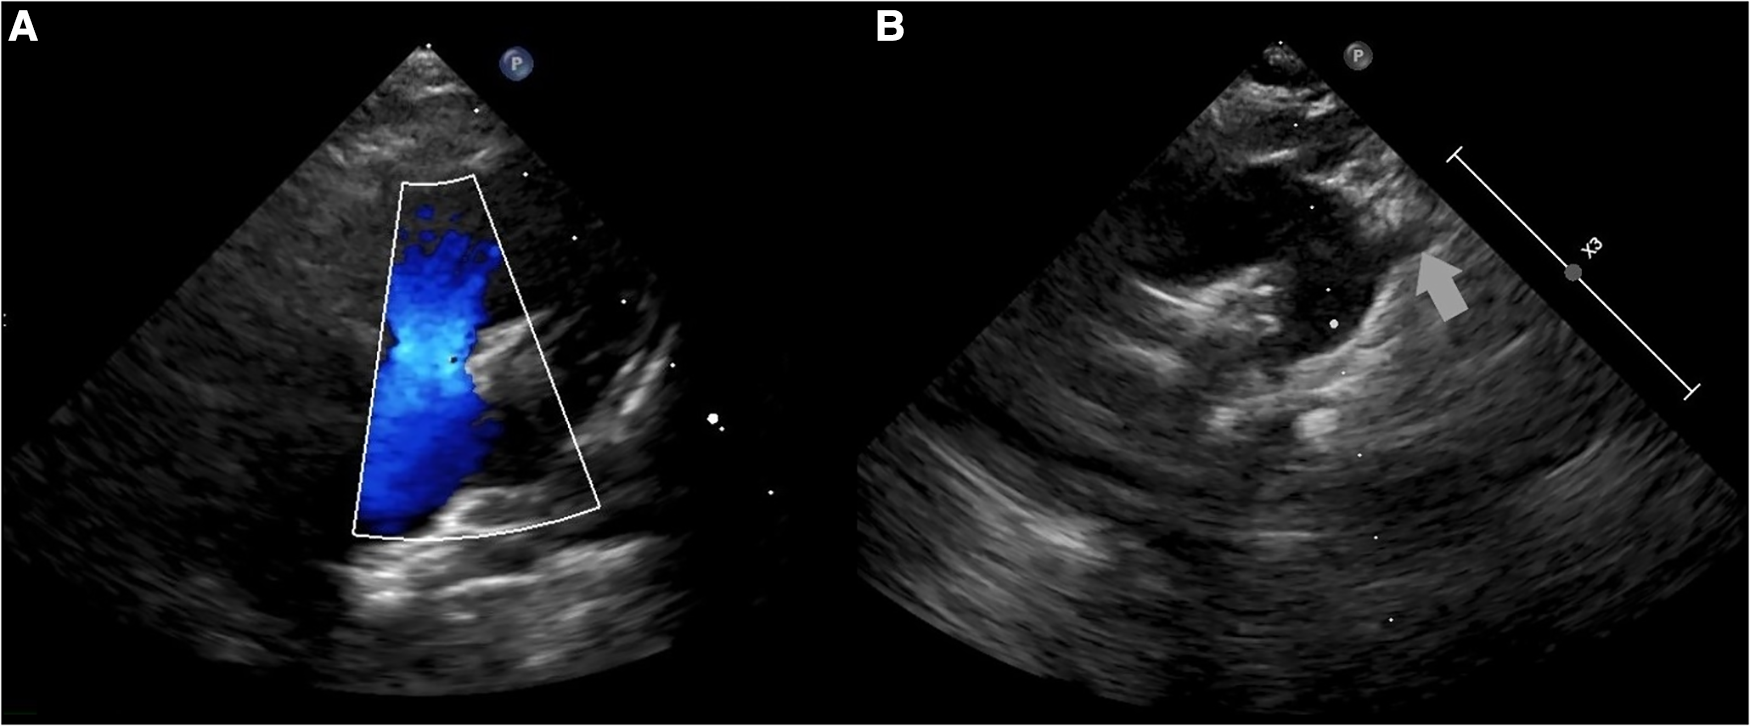

The patient was admitted to the pediatric department for further diagnostic approach. Wheezing persisted for two days and subsided without any specific treatment. A transthoracic echocardiogram revealed absence of the left pulmonary artery, and right arch of aorta and anomaly of subclavian arteries was suspected (Figure 2). No other congenital heart defects or signs of pulmonary hypertension were noted. The diagnosis was confirmed by computed tomography (CT) scans of the chest that demonstrated elongation of the aorta and an aberrant right subclavian artery with Kommerell's diverticulum (KD) (Figure 3A), as well as absence of the left pulmonary artery (Figure 3B), with a hypoplastic upper lobe of the left lung. Atypical vascular branches dividing from the aorta and forming the vasculature of the left lung were also visible (Figure 3C, Supplementary File S1). The mediastinum was slightly shifted to the left. We suspect that atypical vascular branches are aortopulmonary collaterals. Flow supply through ductus arteriosus to the atypical hilar segment of left pulmonary artery could be suspected as well but only angiography could specify the exact anatomy of those branches. We clarified that there is no compression to the airways of vasculature structures during bronchoscopy.

Figure 2. A transthoracic echocardiogram: (A) color Doppler flow not registered in the left pulmonary artery; (B) suspected right arch of aorta and anomaly of subclavian arteries.

Heart and mediastinal displacement, ipsilateral elevation of the diaphragm, and contralateral hyperinflation are observed on chest radiographs in patients with isolated UPAA, whereas KD can only be diagnosed after chest CT or magnetic resonance imaging (MRI) (1, 3–6). Similar abnormalities of UPAA on chest radiography were observed in our patient. An abnormal x-ray scan led to a detailed examination. A transthoracic echocardiogram revealed the absence of the left pulmonary artery and was suspicious for malformations of the aortic arch vessels. Other researchers also reported cases of asymptomatic UPAA incidentally suspected after abnormal findings in the chest x-ray image (3, 4). A contrast-enhanced chest CT scan was sufficient to confirm the diagnosis of left UPAA, and it enabled us to detect an asymptomatic, extremely rare type of KD (1, 3, 4). Chest MRI or ventilation-perfusion scintigraphy can also be used to diagnose UPAA (1).